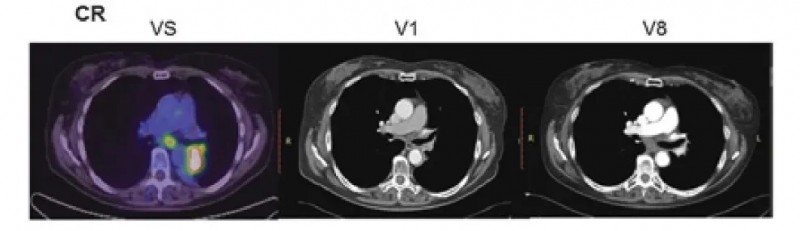

1、完全缓解(CR)病例:INT组(NK细胞+同步放化疗)1例CR患者,基线检查(VS)时,纵隔淋巴结与左肺门的靶病变清晰可见;但在同步放化疗后的首次随访(V1)、及随机分组后18个月的随访(V8)中,两处靶病变均完全消失,最终达到完全缓解(CR)。

▲图源“AACR”,版权归原作者所有,如无意中侵犯了知识产权,请联系我们删除